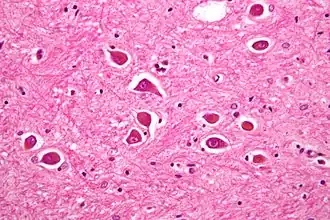

Hepatische encefalopathie[1] ofwel leverencefalopathie[1] wordt, zoals de naam ook zegt, veroorzaakt door ziekten van de lever (hepatisch - van de lever, enképhalos - hersenen, páthos - ziekte). Hepatische encefalopathie treedt op bij ernstig leverfalen, onder andere ten gevolge van cirrose. Waarschijnlijk is een verhoogd ammoniakgehalte de belangrijkste factor, hoewel andere afbraakproducten ook een rol kunnen spelen. Ammoniak wordt normaal gesproken in de lever omgezet tot ureum, dat in de nieren actief uitgescheiden wordt.